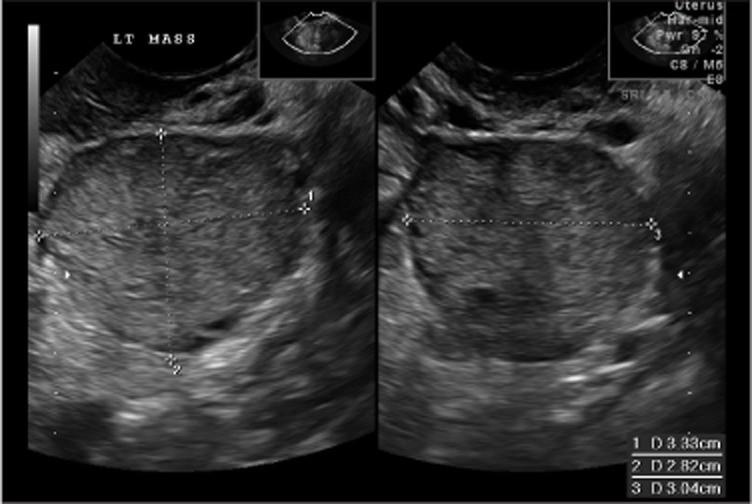

Symptoms or exam findings should lead to imaging study

Pelvic ultrasound is usually first step, CT scan acceptable

No defining ultrasound characteristics for malignant germ cell tumors

Most commonly these are unilateral tumors (1 ovary affected)